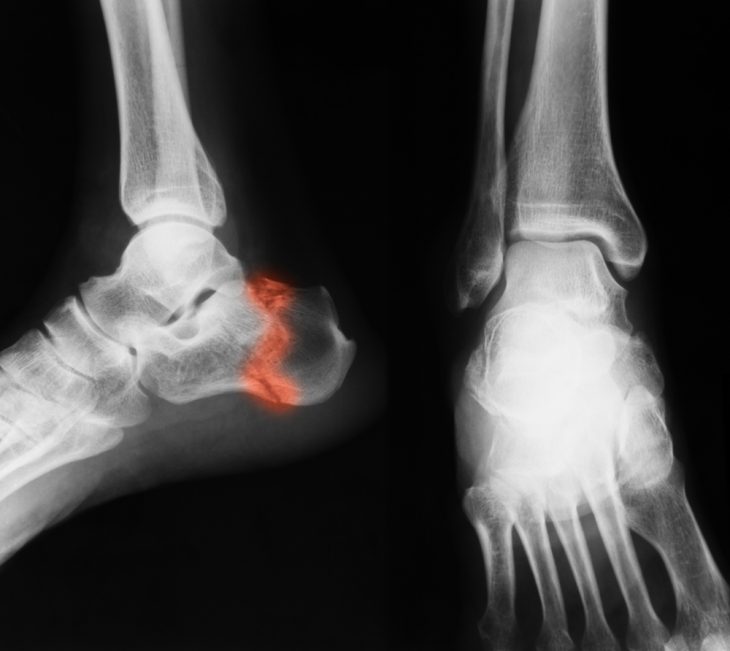

Диагностика

Для выявления перелома пяточной кости всегда проводится рентгенография. Этот метод исследования является «золотым» стандартом при диагностике таких травм. Для его проведения выполняются снимки в боковой и прямой проекции и при этом обязательно исследуются и другие кости: таранная, медиальная и латеральная лодыжки. При выявлении некоторых симптомов и жалоб больного, указывающих на возможное присутствие дополнительных травм, назначается рентгенография или КТ позвоночного столба.

Тактика лечения перелома пяточной кости определяется типом травмы и степенью нарушения естественного расположения костей. Для этого врач особым способом соединяет на рентгеновском снимке определенные точки костей и получает угол Белера. В норме он составляет 20-40°, а при травме уменьшается или становится отрицательным.